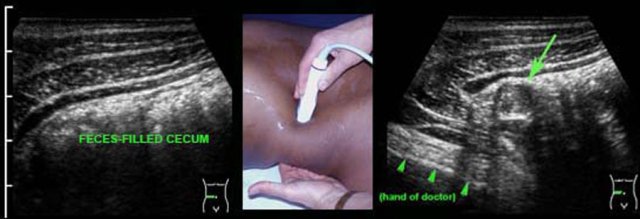

The appendix is usually found at the spot of maximum tenderness.

In retrocecal appendicitis (arrow) the cecum is often pushed medially with the US probe, so that the appendix (arrow) appears to be localized lateral to the cecum than behind it.

Another possibility to visualize the appendix in retrocecal appendicitis is positioning of the probe in the right flank, thereby avoiding the gas and feces-filled cecum.

Another trick in retrocecal appendicitis is to push the inflamed appendix (arrow) with your left hand in the direction of the probe.

To find the appendix, it may be useful at first to identify the ileocecal valve (see also US of the GI tract: normal anatomy).

The base of the appendix is usually found 3 centimeters caudally, where it leaves the cecal pole at the medial side.